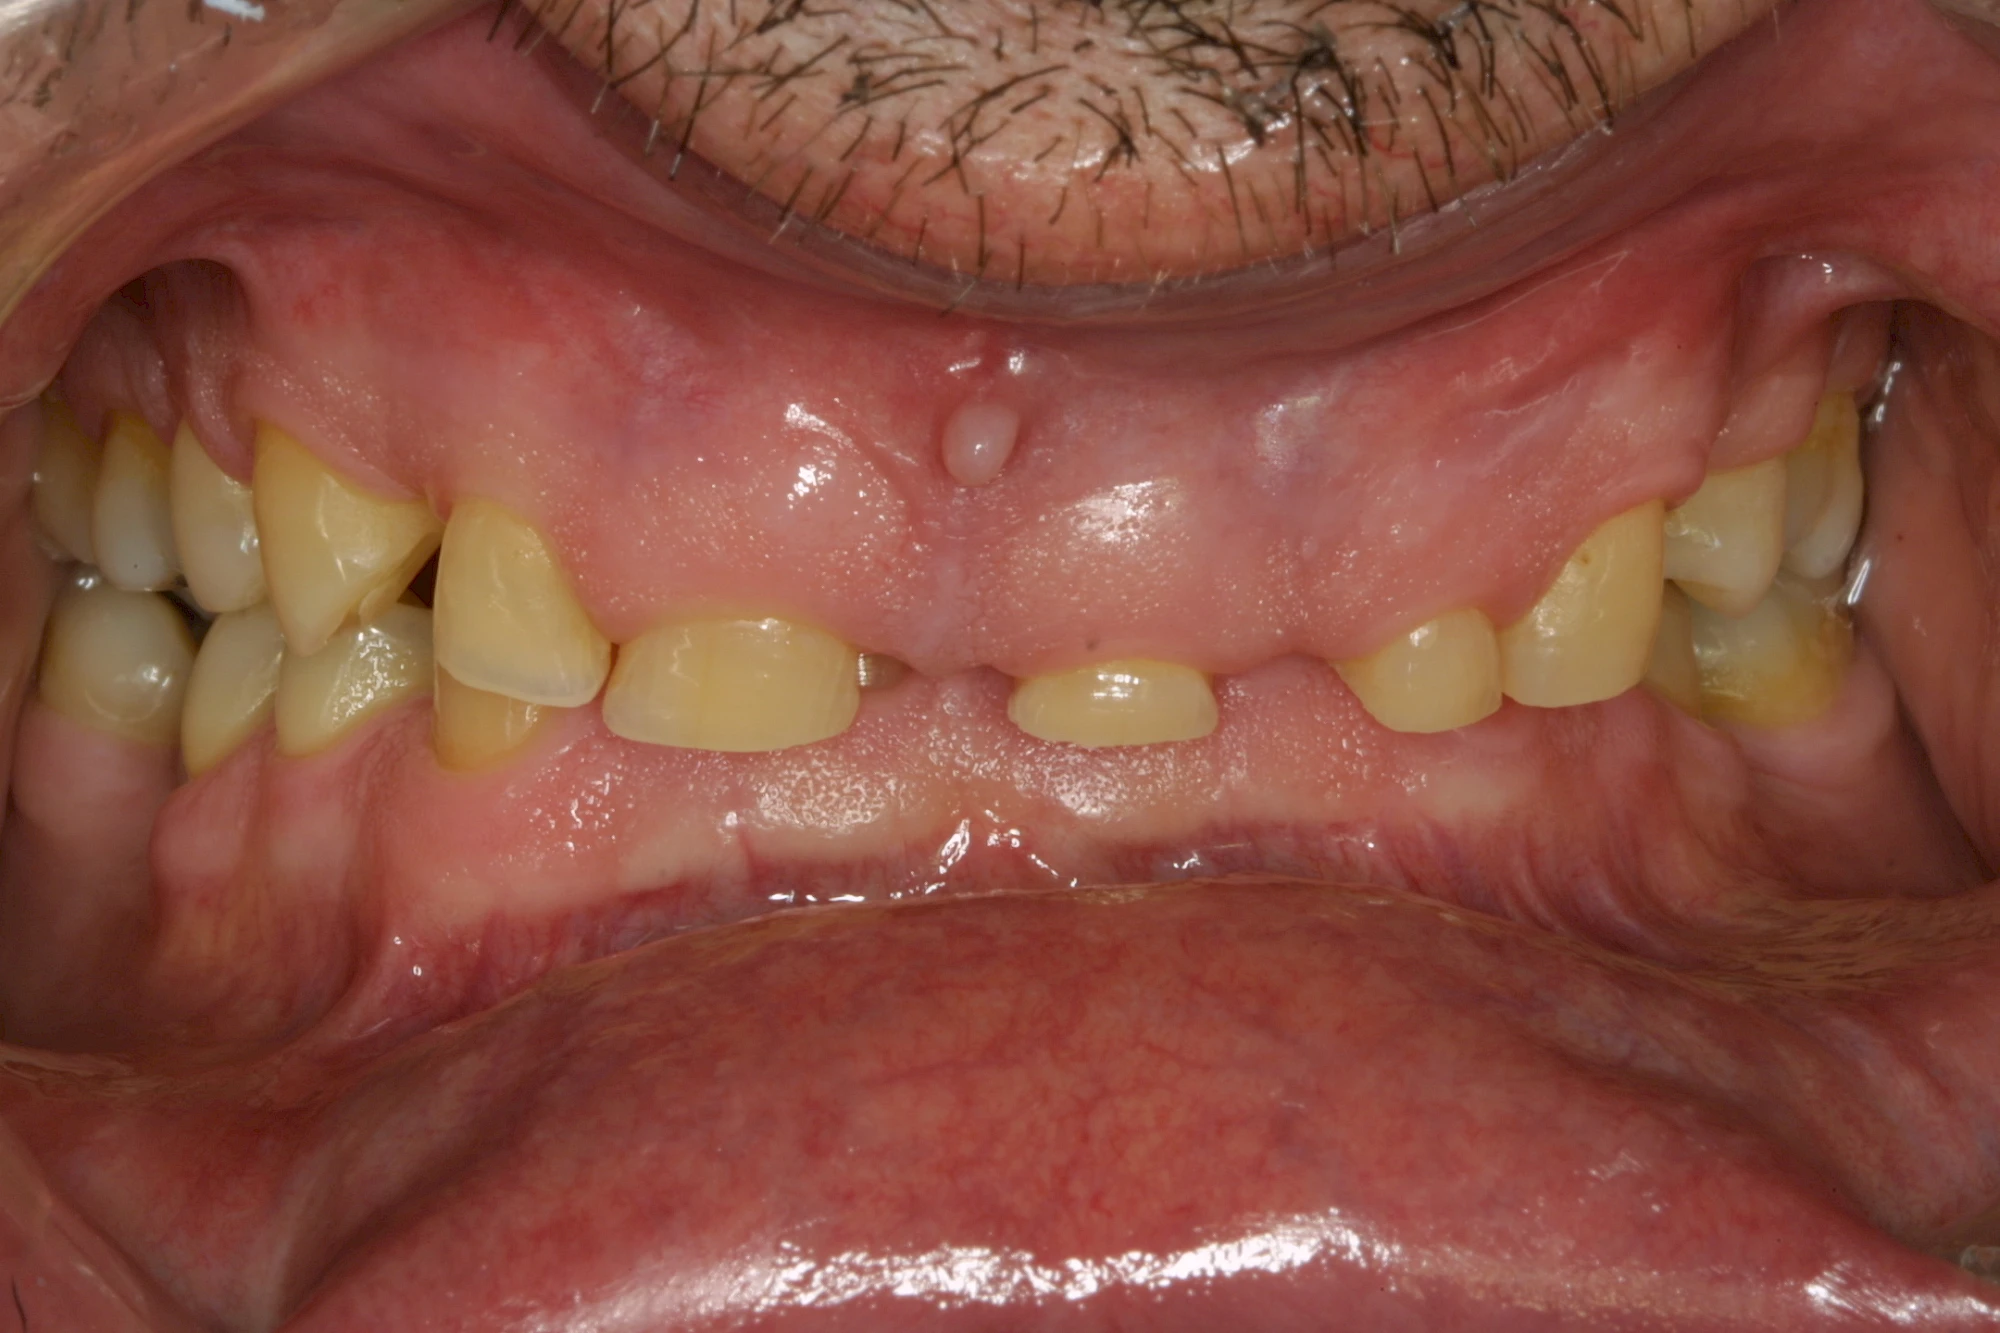

Keilförmiger Defekt

Eine Sonderform sind sogenannte keilförmige Defekte im Bereich der Zahnhälse. Hier geht man davon aus, dass Knirschen und Pressen in Kombination mit falschen Putzgewohnheiten (zu hoher Putzdruck, Verwendung von Zahnpasta mit hohen Abrasionswerten) eine Rolle spielen.